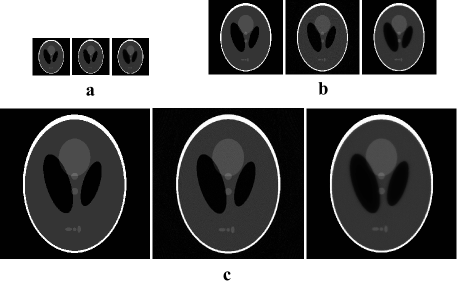

Experiment 4: In order to verify the feasibility of SLT algorithm, this experiment performs image reconstruction with the SRM calculated by SLT algorithm. Reconstructed images are Shepp-Logan of 128×128128128128\times 128, 256×256256256256\times 256, 512×512512512512\times 512, and this experiment uses ART and MLEM to iterate 100 times, the result is shown in Fig. 8. In addition, in order to evaluate the performance of the algorithm better, this experiment uses FBP for 100 times repeated reconstructions and adds 64×64646464\times 64 Shepp-Logan reconstruction. Their numerical results of the reconstruction are shown in Table 3 and Fig. 9.

Refer to caption

Figure 8: Reconstruction of Shepp-Logan of different sizes. In each subfigure, the order from left to right is the original image, reconstructed image by ART algorithm and reconstructed image by MLEM algorithm. \figfooteraReconstruction of Shepp-Logan of size 128×128128128128\times 128 \figfooterbReconstruction of Shepp-Logan of size 256×256256256256\times 256 \figfootercReconstruction of Shepp-Logan of size 512×512512512512\times 512

As shown in Table 3, when reconstructing Shepp-Logan of different sizes, FBP takes the minimum time and MLEM takes the maximum time. Fig. 9 shows that the accuracy of FBP is always worst. When the Shepp-Logan size is 64×64646464\times 64, the ART algorithm is superior than the MLEM algorithm by an order of magnitude in accuracy. However, with the increase of the Shepp-Logan size, the variance of the ART algorithm is larger, and the SNR is reduced accordingly. But the variance and SNR of the MLEM algorithm change less, so the accuracy of the MLEM algorithm first approaches and then even exceeds the ART algorithm. According to the above analysis, we know FBP has high real-time capability but low precision. ART and MELM are high precision but time-consuming. It can also be seen that ART and MLEM have their specific advantages and disadvantages on the reconstruction based on SLT. Those above results prove that the SLT algorithm of this paper has certain significance for image reconstruction.